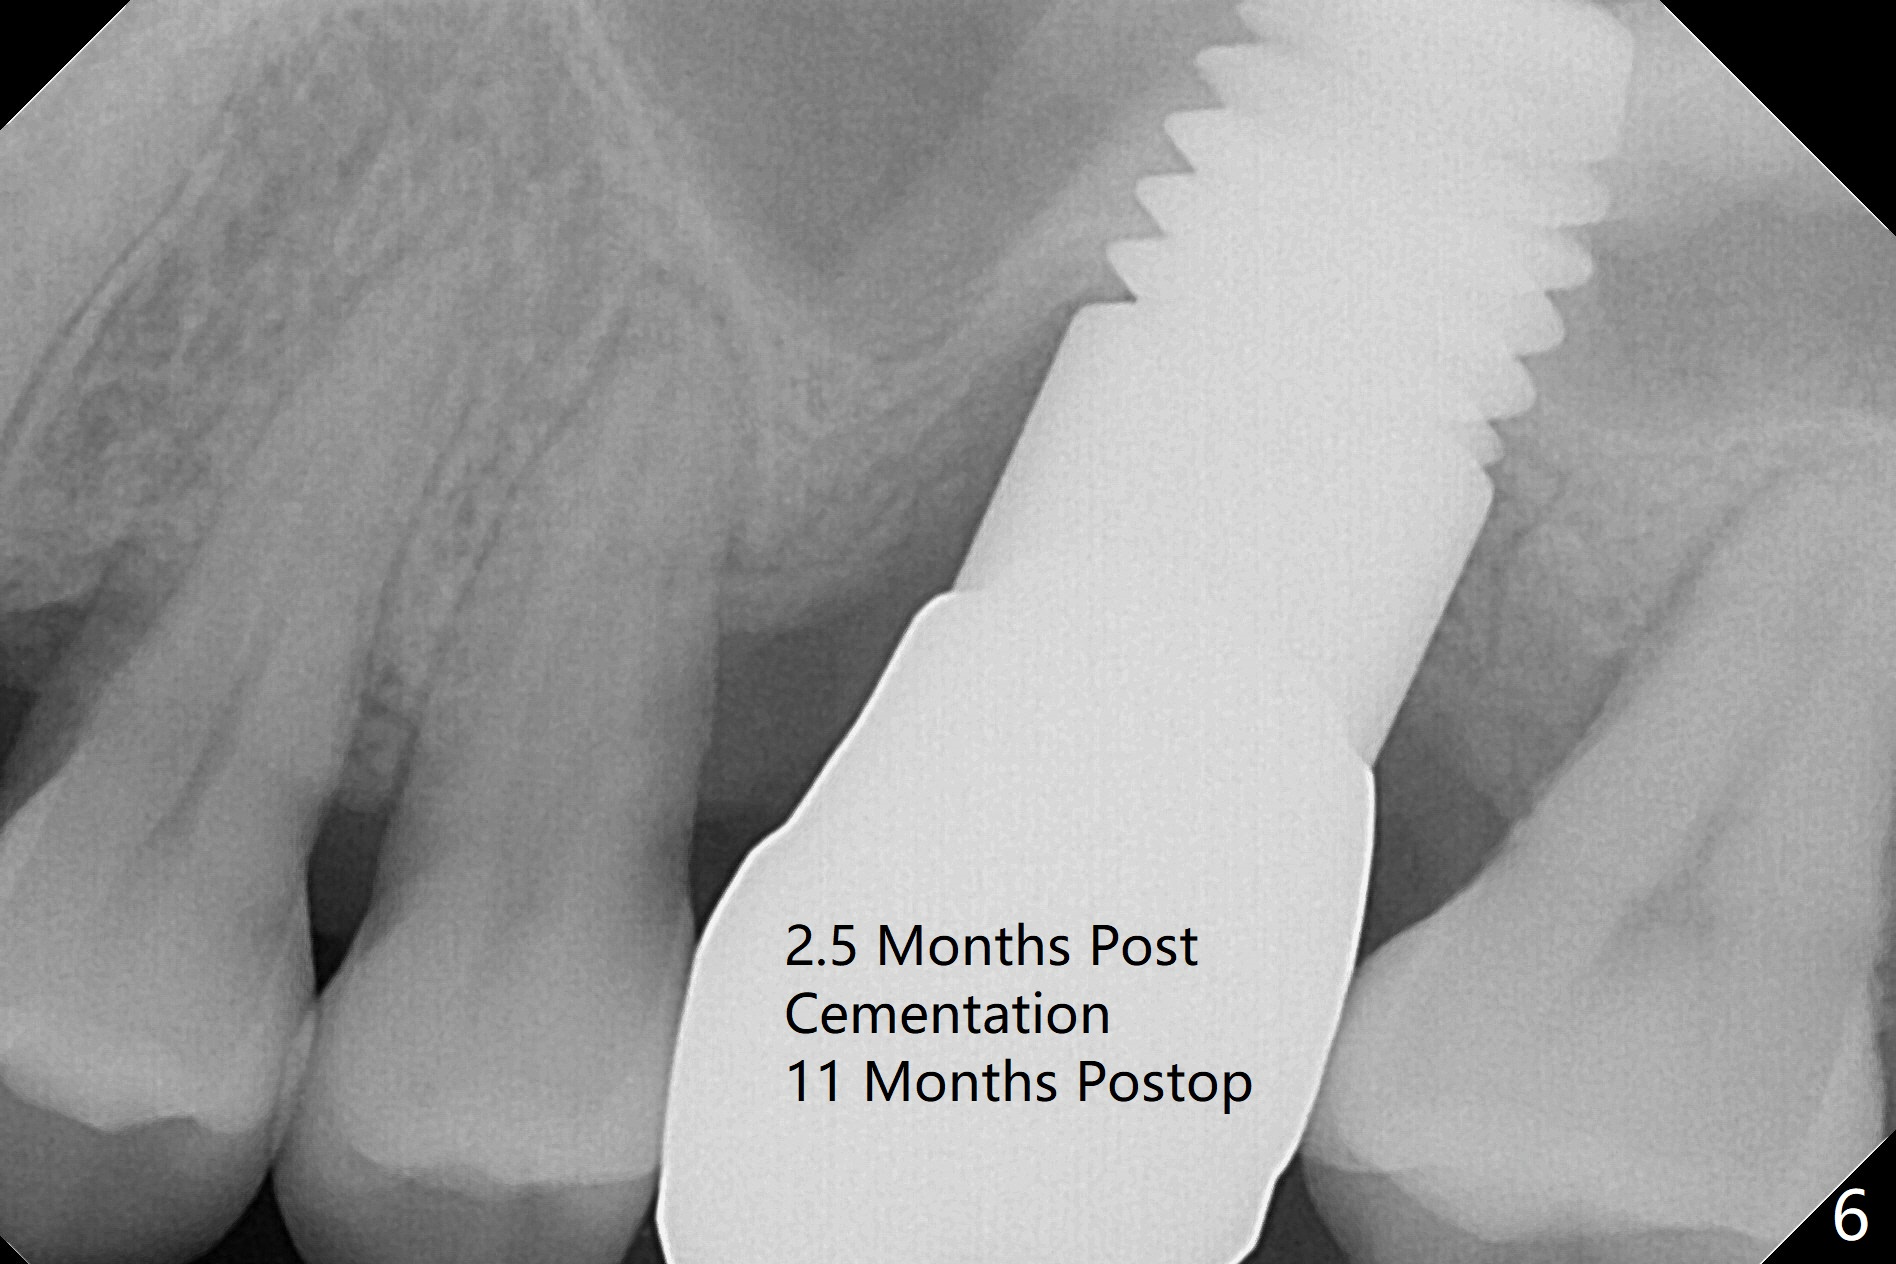

Three months post cementation, the implant at #14 is found loose (Fig.1: 6.5x11 mm) and removed. After removal of minimal granulation tissue, normal saline disappears into the apical end of osteotomy. In fact there is no bone apically, although the sinus membrane is intact. After try in of various taps (tapered and cylindrical, bone- and tissue-level), a 8x14 mm dummy implant is placed (Fig.2), followed by Osteogen plug and the same sized definitive implant, which has to be placed deeper to obtain ~ 45 Ncm (Fig.3). There is minimal thread engagement. If the implant fails, place 2 layers of PRF membrane apically, bone graft and 1 layer of PRF coronally for ridge preservation. A healing abutment will be placed to expose the coronal end of the implant ~ 4 months postop. The tissue-level implant remains subgingival 4.5 months postop (Fig.4). A 8 mm healing cuff cannot be placed even after laser gingivectomy. The implant is 2 mm subcrestal mesially. Torque wrench cannot reverse the implant at 60 Ncm. The implant is later reversed with Tatum wrench until it is turned with the torque wrench at 30 Ncm. The implant remains stable, while the healing cuff with Triple Antibiotic Ointment is placed. The healing cuff is stable 2 weeks later (Fig.5 C). With progressive loading for a month, a crown is cemented 9 months postop. There appears no bone loss 2.5 months post cementation (11 months postop, Fig.6). Return to Upper Molar Immediate Implant, Armaments, IBS #3 Xin Wei, DDS, PhD, MS 1st edition 04/30/2018, last revision 04/14/2019